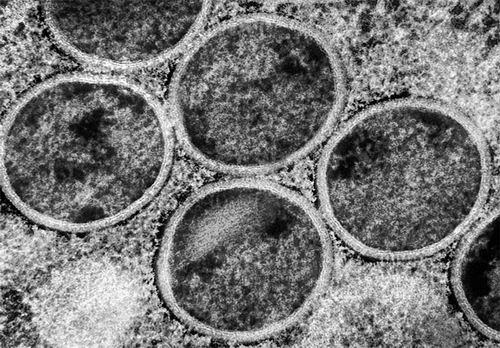

猴痘病毒持续进化与传播风险,对男性生育能力潜在影响引关注(图1)

猴痘病毒似乎更容易在人与人之间传播。图片来源:NIAID/SPL